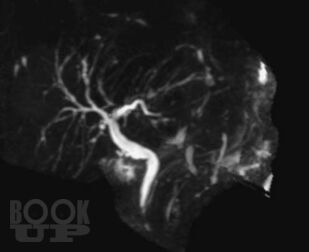

Магнитно-резонансная холангиопанкреатография

В монографии представлены современные сведения о магнитно-резонансной холангиопанкреатографии (МРХПГ). Детально отражены технические основы метода, методика и планирование исследования. Рассматриваются причины ошибок при интерпретации данных МРХПГ и способы их предотвращения и преодоления. Приведены базовые протоколы различных видов МРХПГ. Описана нормальная анатомия желчевыводящих протоков, желчного пузыря и протоков поджелудочной железы, изменения желчевыводящих протоков, желчного пузыря и протоков поджелудочной железы при патологических процессах. Отражены вопросы диагностики холангиолитиаза и оценки послеоперационной анатомии желчевыводящих протоков. Рассмотрены особенности МРХПГ при патологических изменениях комплекса большого дуоденального сосочка и двенадцатиперстной кишки. Приведены данные о МРХПГ с использованием гепатоспецифического контрастного вещества.

Каждый раздел монографии иллюстрирован.